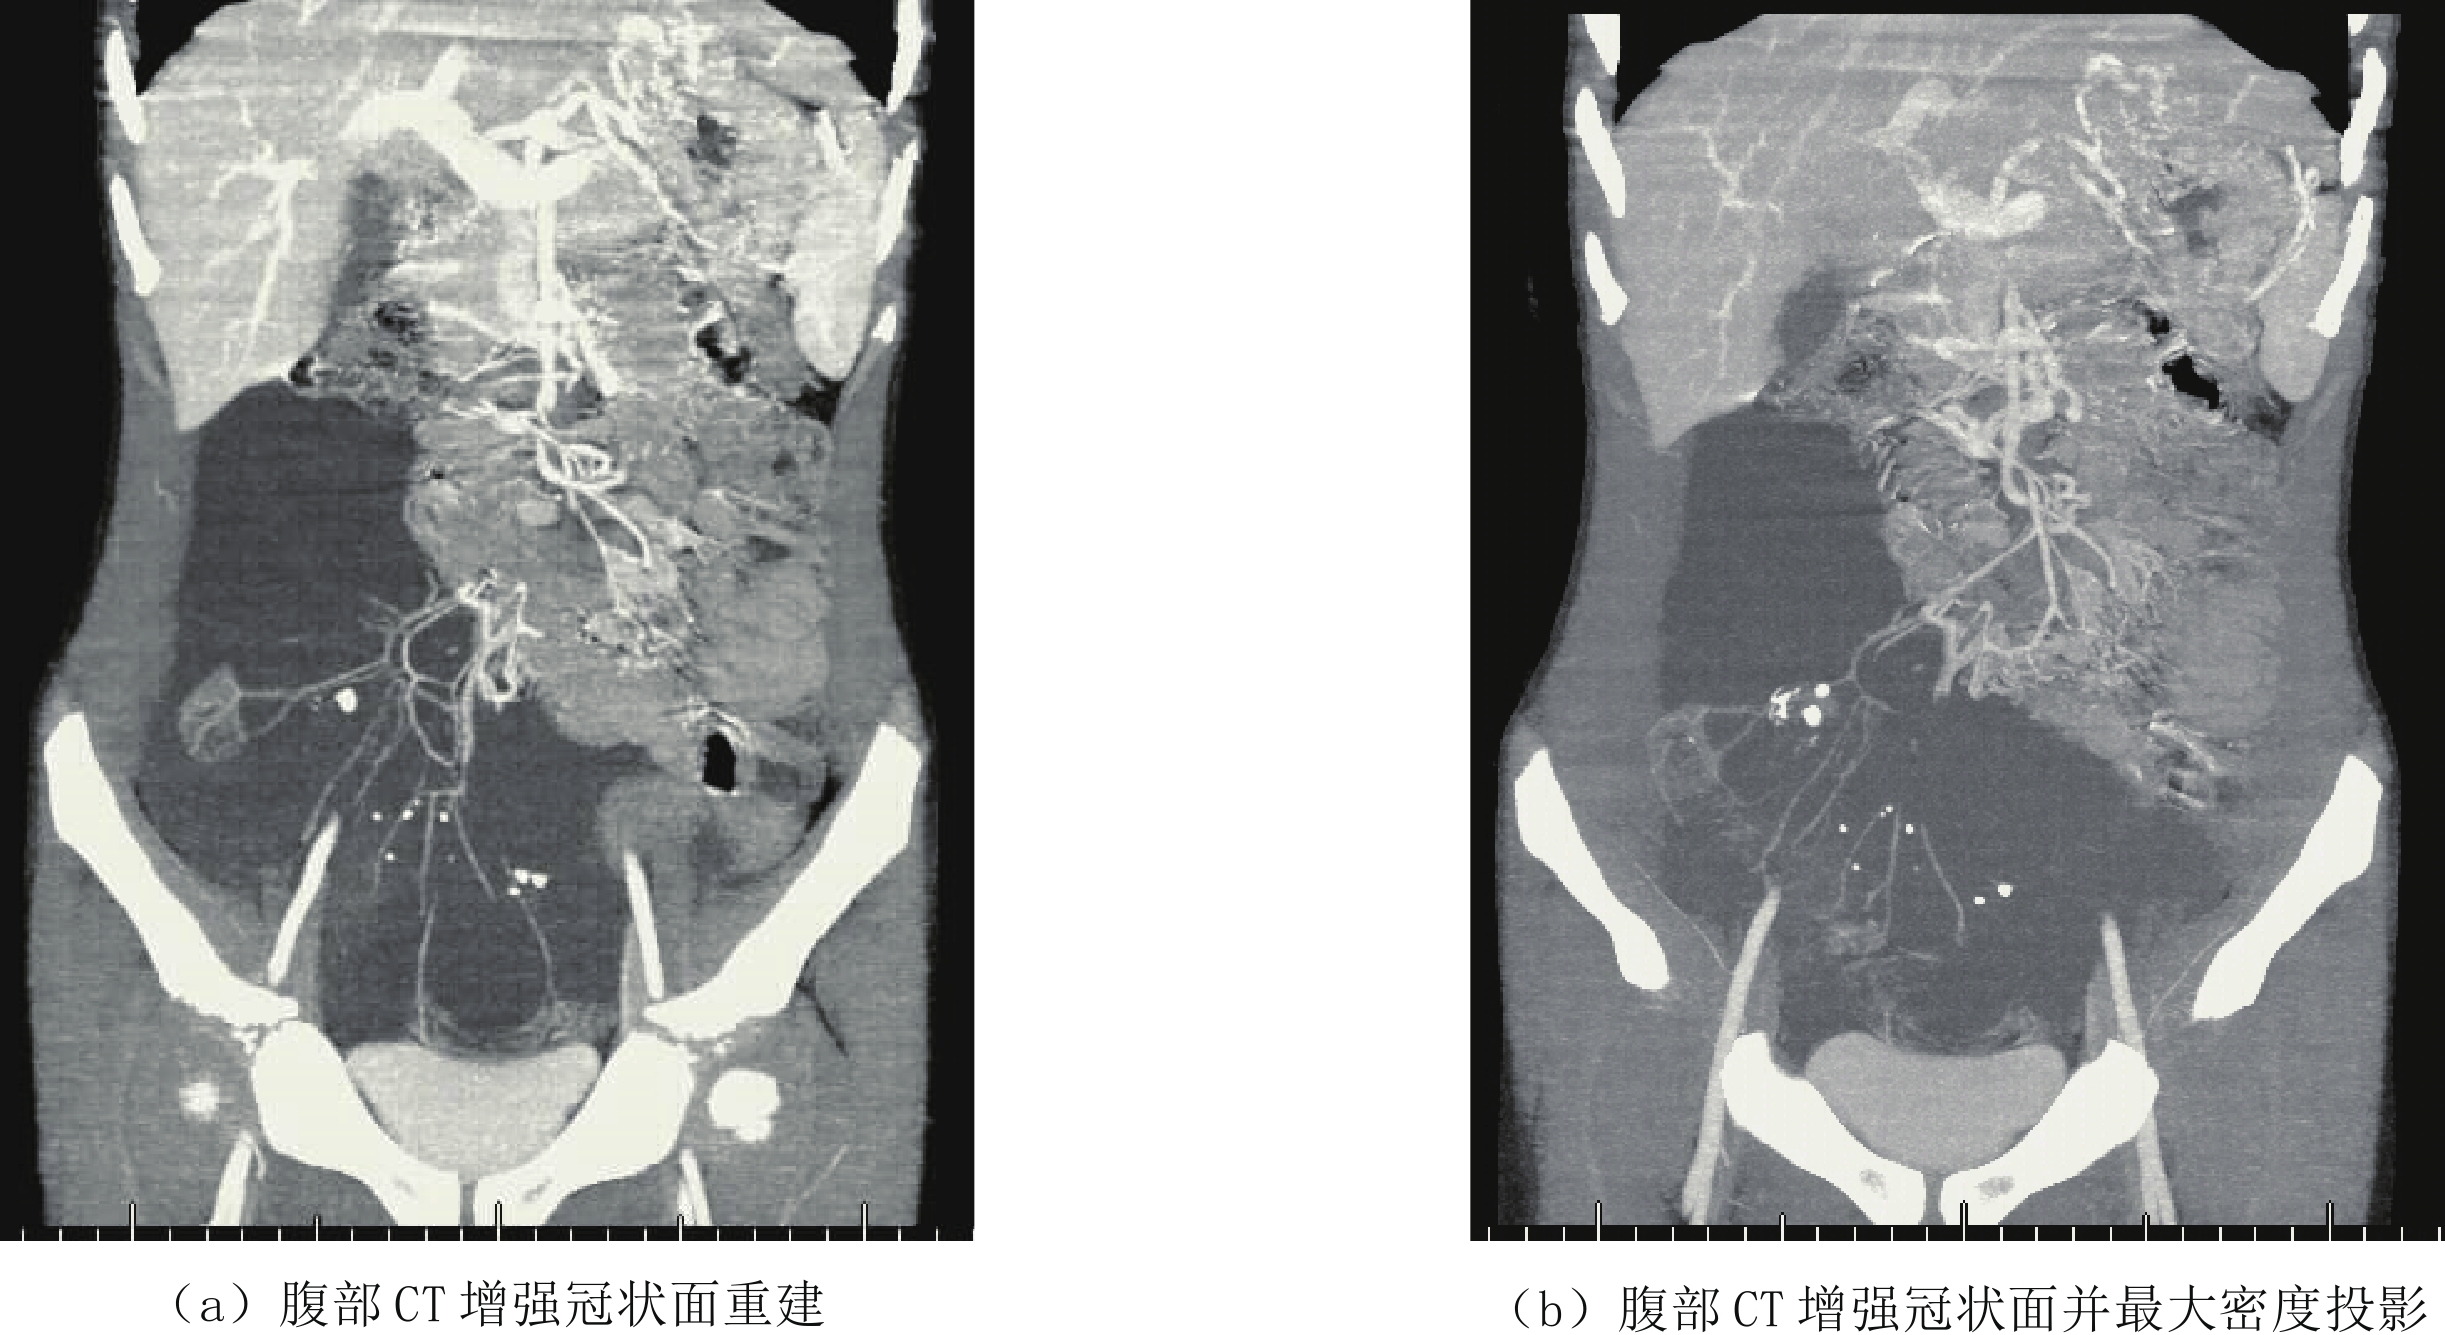

近年来,由于新生儿胸腔手术和中心静脉置管损伤胸导管或大淋巴管导致淋巴液或乳糜液的漏出。对于新生儿乳糜胸影像学检查方法首选胸部X线平片,表现为一侧或双胸腔致密,心缘消失,一侧胸腔积液时,心影纵隔向健侧移位,肋间隙增宽,胸部CT平扫为中-大量胸腔积液,相邻肺脏受压,胸腔穿刺引流,胸腔积液中甘油三酯>1.1 mmol/L,或白细胞计数>1×109/L,且以淋巴细胞为主,即可诊断新生儿乳糜胸(图1)。

![]() 图 1 男,6天。以"生后气促6天"入院。左侧大量胸腔积液,胸水常规检查提示白细胞升高,胸水内甘油三酯含量高—新生儿乳糜胸Figure 1. Male, 6 days old, admitted to hospital with "postnatal shortness of breath for 6 days". Large amount of pleural effusion of the left side. Routine examination of the pleural effusion indicates elevated leukocytes and high triglyceride content in pleural effusion-neonatal chylothorax

图 1 男,6天。以"生后气促6天"入院。左侧大量胸腔积液,胸水常规检查提示白细胞升高,胸水内甘油三酯含量高—新生儿乳糜胸Figure 1. Male, 6 days old, admitted to hospital with "postnatal shortness of breath for 6 days". Large amount of pleural effusion of the left side. Routine examination of the pleural effusion indicates elevated leukocytes and high triglyceride content in pleural effusion-neonatal chylothoraxCLFDs新生儿期或婴幼儿期可以表现为乳糜胸、乳糜腹和淋巴水肿,可以进行性加重,死亡率高。CLFDs分为先天性和继发性。先天性CLFDs主要是由于胸导管或中央淋巴系统发育不良所致,通过DCMRL检查腹膜后、脊柱周围没有正常的胸导管或中央淋巴系统的显示,对比剂通过异常部位的侧枝淋巴管回流。继发性CLFDs是由于各种原因所致的中心静脉压升高,如继发于肺动脉高压、完全性肺静脉异位引流以及中心静脉血栓等,导致淋巴液回流受阻,可行磁共振淋巴管造影(MRL)证实(图2),影像表现为胸导管或中央淋巴系统迂曲扩张,走行分布未见异常,颈部、胸壁、肠系膜水肿,伴胸腔和或腹腔积液。

图 1 男,6天。以"生后气促6天"入院。左侧大量胸腔积液,胸水常规检查提示白细胞升高,胸水内甘油三酯含量高—新生儿乳糜胸

Figure 1. Male, 6 days old, admitted to hospital with "postnatal shortness of breath for 6 days". Large amount of pleural effusion of the left side. Routine examination of the pleural effusion indicates elevated leukocytes and high triglyceride content in pleural effusion-neonatal chylothorax